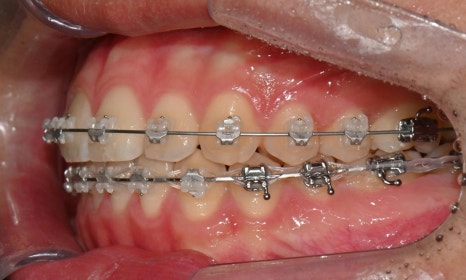

치료 시작 7개월 후 사진으로, 치아 배열 후 아래 우측에 미니스크류를 식립하여 치아 중심선을 개선하는 중으로, 교합과 치아 중심선이 많이 개선된 것을 확인할 수 있습니다.